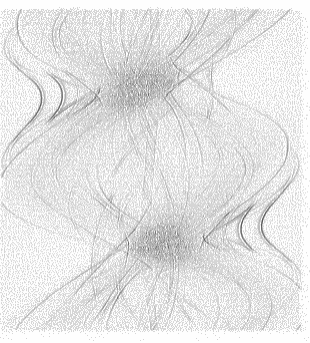

Low-Dose Computed Tomography (LDCT) technique, which reduces the radiation harm to human bodies, is now attracting increasing interest in the medical imaging field. As the image quality is degraded by low dose radiation, LDCT exams require specialized reconstruction methods or denoising algorithms. However, most of the recent effective methods overlook the inner-structure of the original projection data (sinogram) which limits their denoising ability. The inner-structure of the sinogram represents special characteristics of the data in the sinogram domain. By maintaining this structure while denoising, the noise can be obviously restrained. Therefore, we propose an LDCT denoising network namely Sinogram Inner-Structure Transformer (SIST) to reduce the noise by utilizing the inner-structure in the sinogram domain. Specifically, we study the CT imaging mechanism and statistical characteristics of sinogram to design the sinogram inner-structure loss including the global and local inner-structure for restoring high-quality CT images. Besides, we propose a sinogram transformer module to better extract sinogram features. The transformer architecture using a self-attention mechanism can exploit interrelations between projections of different view angles, which achieves an outstanding performance in sinogram denoising. Furthermore, in order to improve the performance in the image domain, we propose the image reconstruction module to complementarily denoise both in the sinogram and image domain.